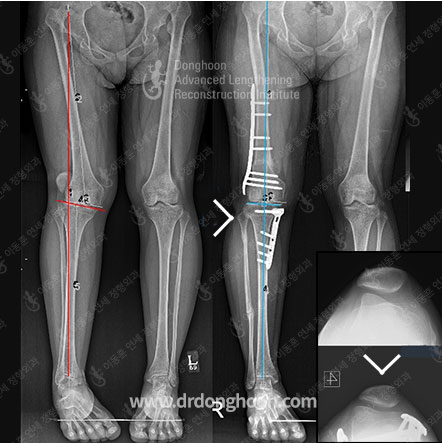

例1 誤った骨切りの位置によって関節線(jointline)の傾きが増加した合併症を、再手術を通して矯正する

脚の変形(曲がった脚)の正確な位置を分析して 変形のある位置で 矯正手術を行う

外側から同じ模様の曲がった脚(O脚またはX脚など)だとしても、実際に脚が曲がった位置はそれぞれ異なることがあります。O脚の場合はふくらはぎの骨(脛骨)に、X脚の場合は太ももの骨(大腿骨)に変形がある場合が多いですが、常にそうであるのではないために常に正確な分析が必要です。

またどんな変形であっても正確に分析をして治療が可能な医療陣と共に治療を行って下さい。実際の変形位置と関係なしに手術をした場合、外側からは良くなったように見えるかも知れませんが、実際にはまた別の変形を作る結果を招くことがあります

例2 太ももの骨及びふくらはぎの骨の複合変形により発生したX脚変形・関節線の傾き変形及び大腿膝蓋関節の問題を、三次元的な骨切り術を通して治療する